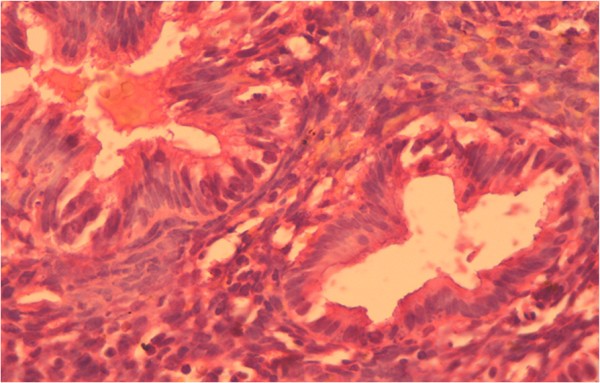

The content of estradiol and progesterone receptors in epithelial cells and stroma with glandular cystic hyperplasia of the endometrium with immunohistochemical study is presented in Figure 2.

Figure 2

Glandular cystic hyperplasia. Coloring by hematoxylin-eosin (×40).

In patients with glandular cystic hyperplasia, the concentration of estradiol receptors in epithelial cells was significantly higher as compared to that in the control group. Thus, the content of estradiol receptors in epithelial cells was 75.6%, while the rate in the control group was 43.3% (Figure 3).

Our findings did not show significant changes in stromal content in these groups (30.9% in the group with glandular hyperplasia and 29.6% in the control group). In our opinion, this is due to the type of hyperplasia. Glandular cystic hyperplasia is usually characterized by irregular proliferation of glandular and stromal components due to irregular activation of the receptor system of glands and stroma; the number of progesterone receptors in epithelial cells and stroma in patients with glandular cystic hyperplasia was slightly higher than in the control group (69.3% in the epithelial cells and 62.2% in the stroma in patients with glandular cystic hyperplasia; 52.4% and 48.5% in the control group, respectively). This fact confirms the role and relative hyperestrogenemia and hypoprogesteronemia at the cellular level for the proliferative state of the endometrium. As the results of our research, the hormone levels do not always determine the degree of proliferation; a significant role in the pathogenesis of endometrial hyperplasia has a certain value of steroid hormone receptors that causes the sensitivity of endometrial cells.

Immunohistochemical reaction in the endometrium with glandular cystic hyperplasia of antibodies with estrogen and progesterone is shown in Figures 4 and 5.